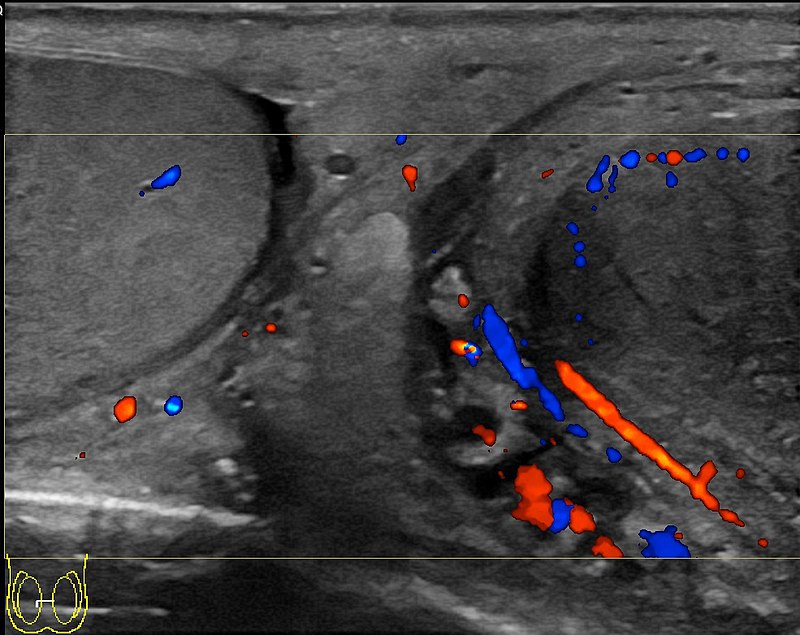

Varicocele is the dilation of the spermatic vein because of impaired drainage.

Varicocele presents as a “bag of worms” like scrotal enlargement.

Varicoceles are typically left sided.

The left testicular vein drains into the left renal vein.

Varicoceles may be seen in the setting of left-sided renal cell carcinoma.